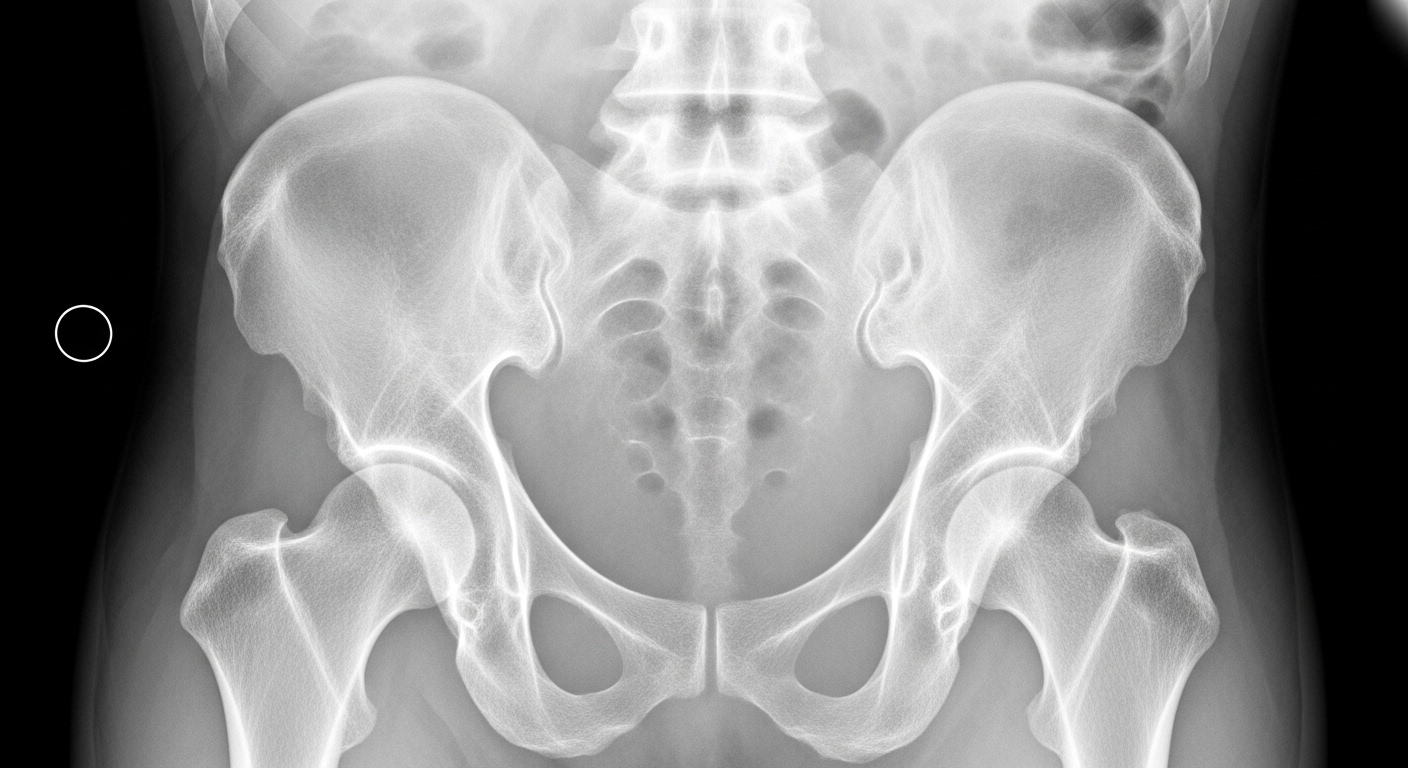

レントゲンは骨の形や関節の隙間を確認する検査です。

しかし、軟骨や筋肉、腱、関節唇といった軟部組織までは映りません。

そのため、初期の段階で起こる以下のようなトラブルは、

レントゲンだけでは判断できないのです。